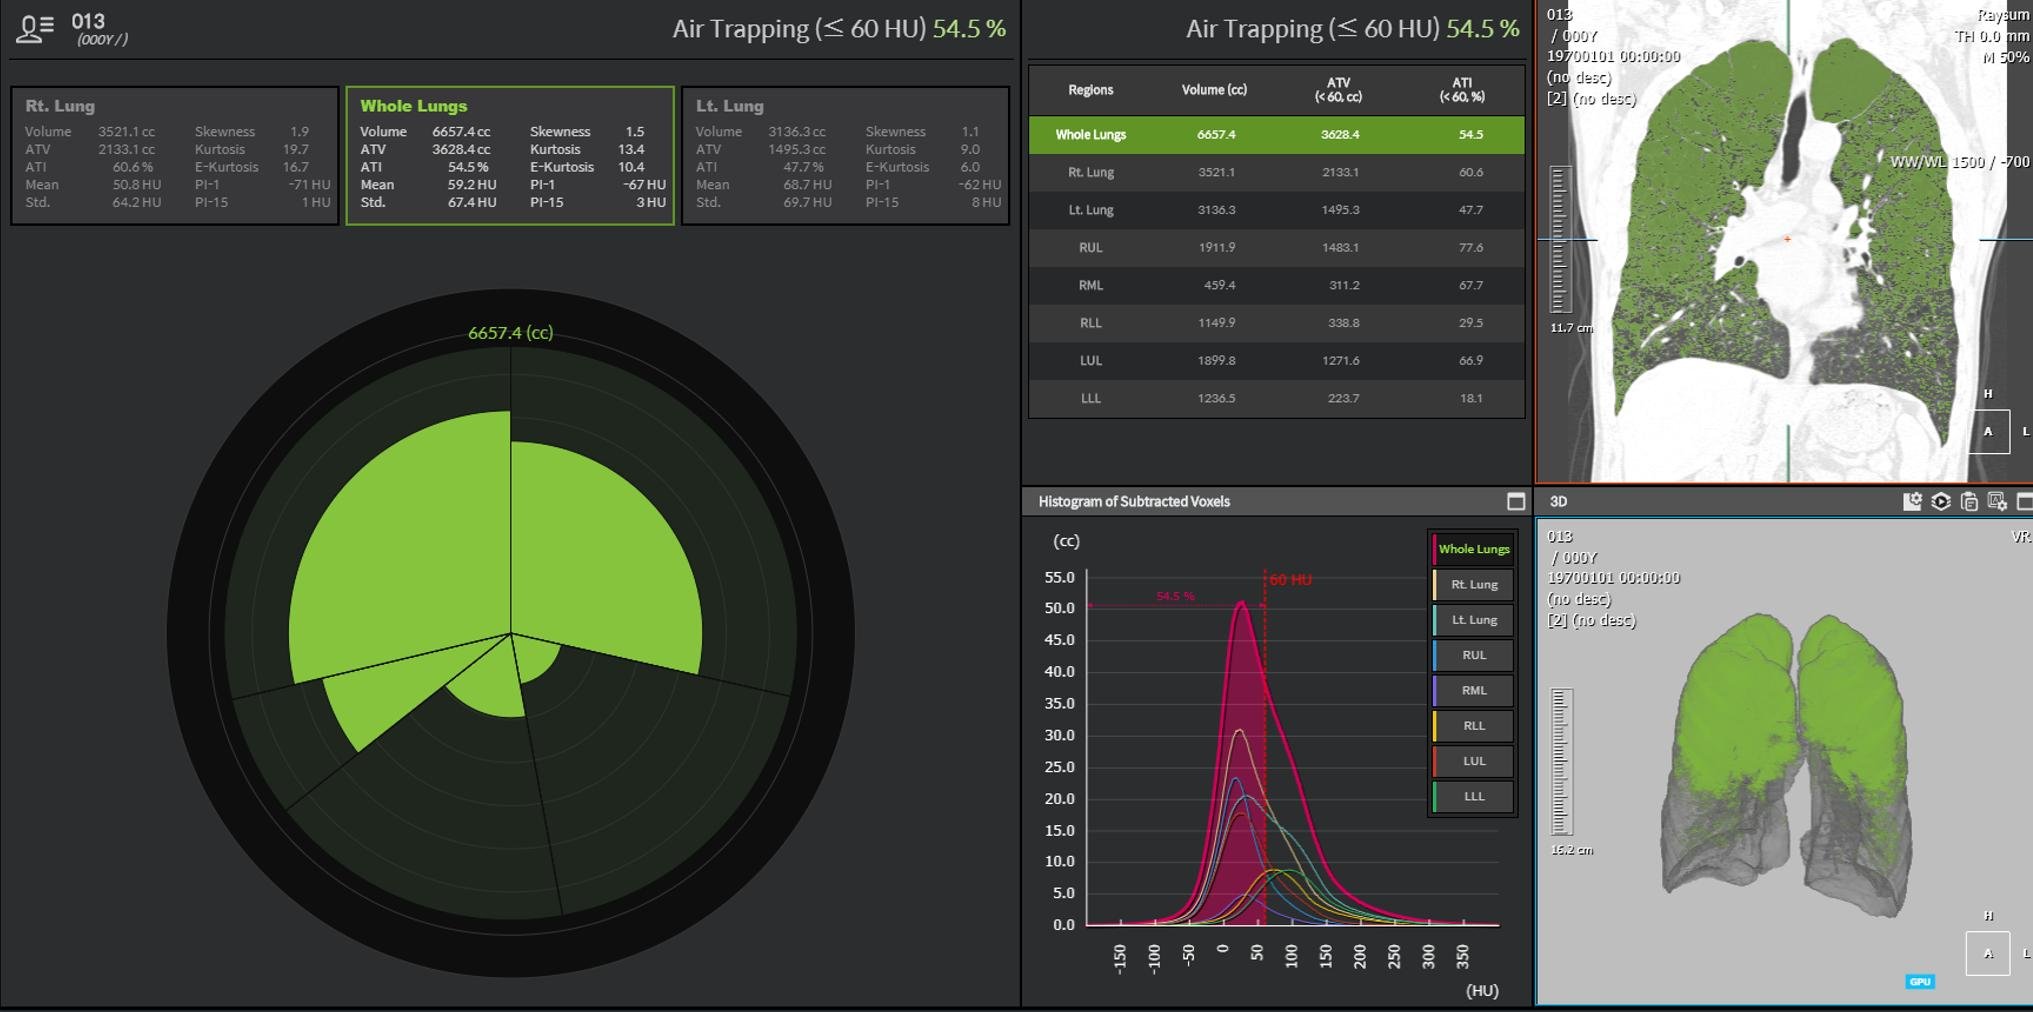

- Functional imaging of large and small airways

- Imaging of COPD and smoking-related disease